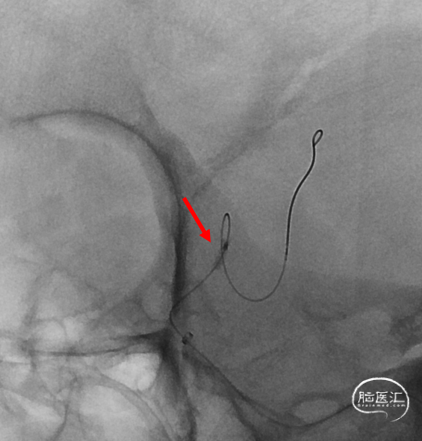

支架打开不良

支架重新打开良好

再次交换3m Floppy

Maverick 2mm/15mm,6atm